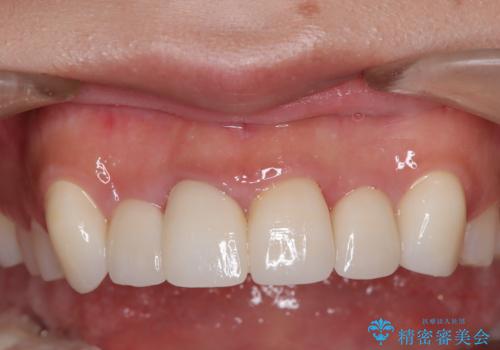

歯肉の治りを待ったうえで(約8か月)、最終補綴することとなりました。

補綴はスペシャルです。

結果的に期間がかなりかかってしまいましたが、患者様に満足していただける結果となりました。